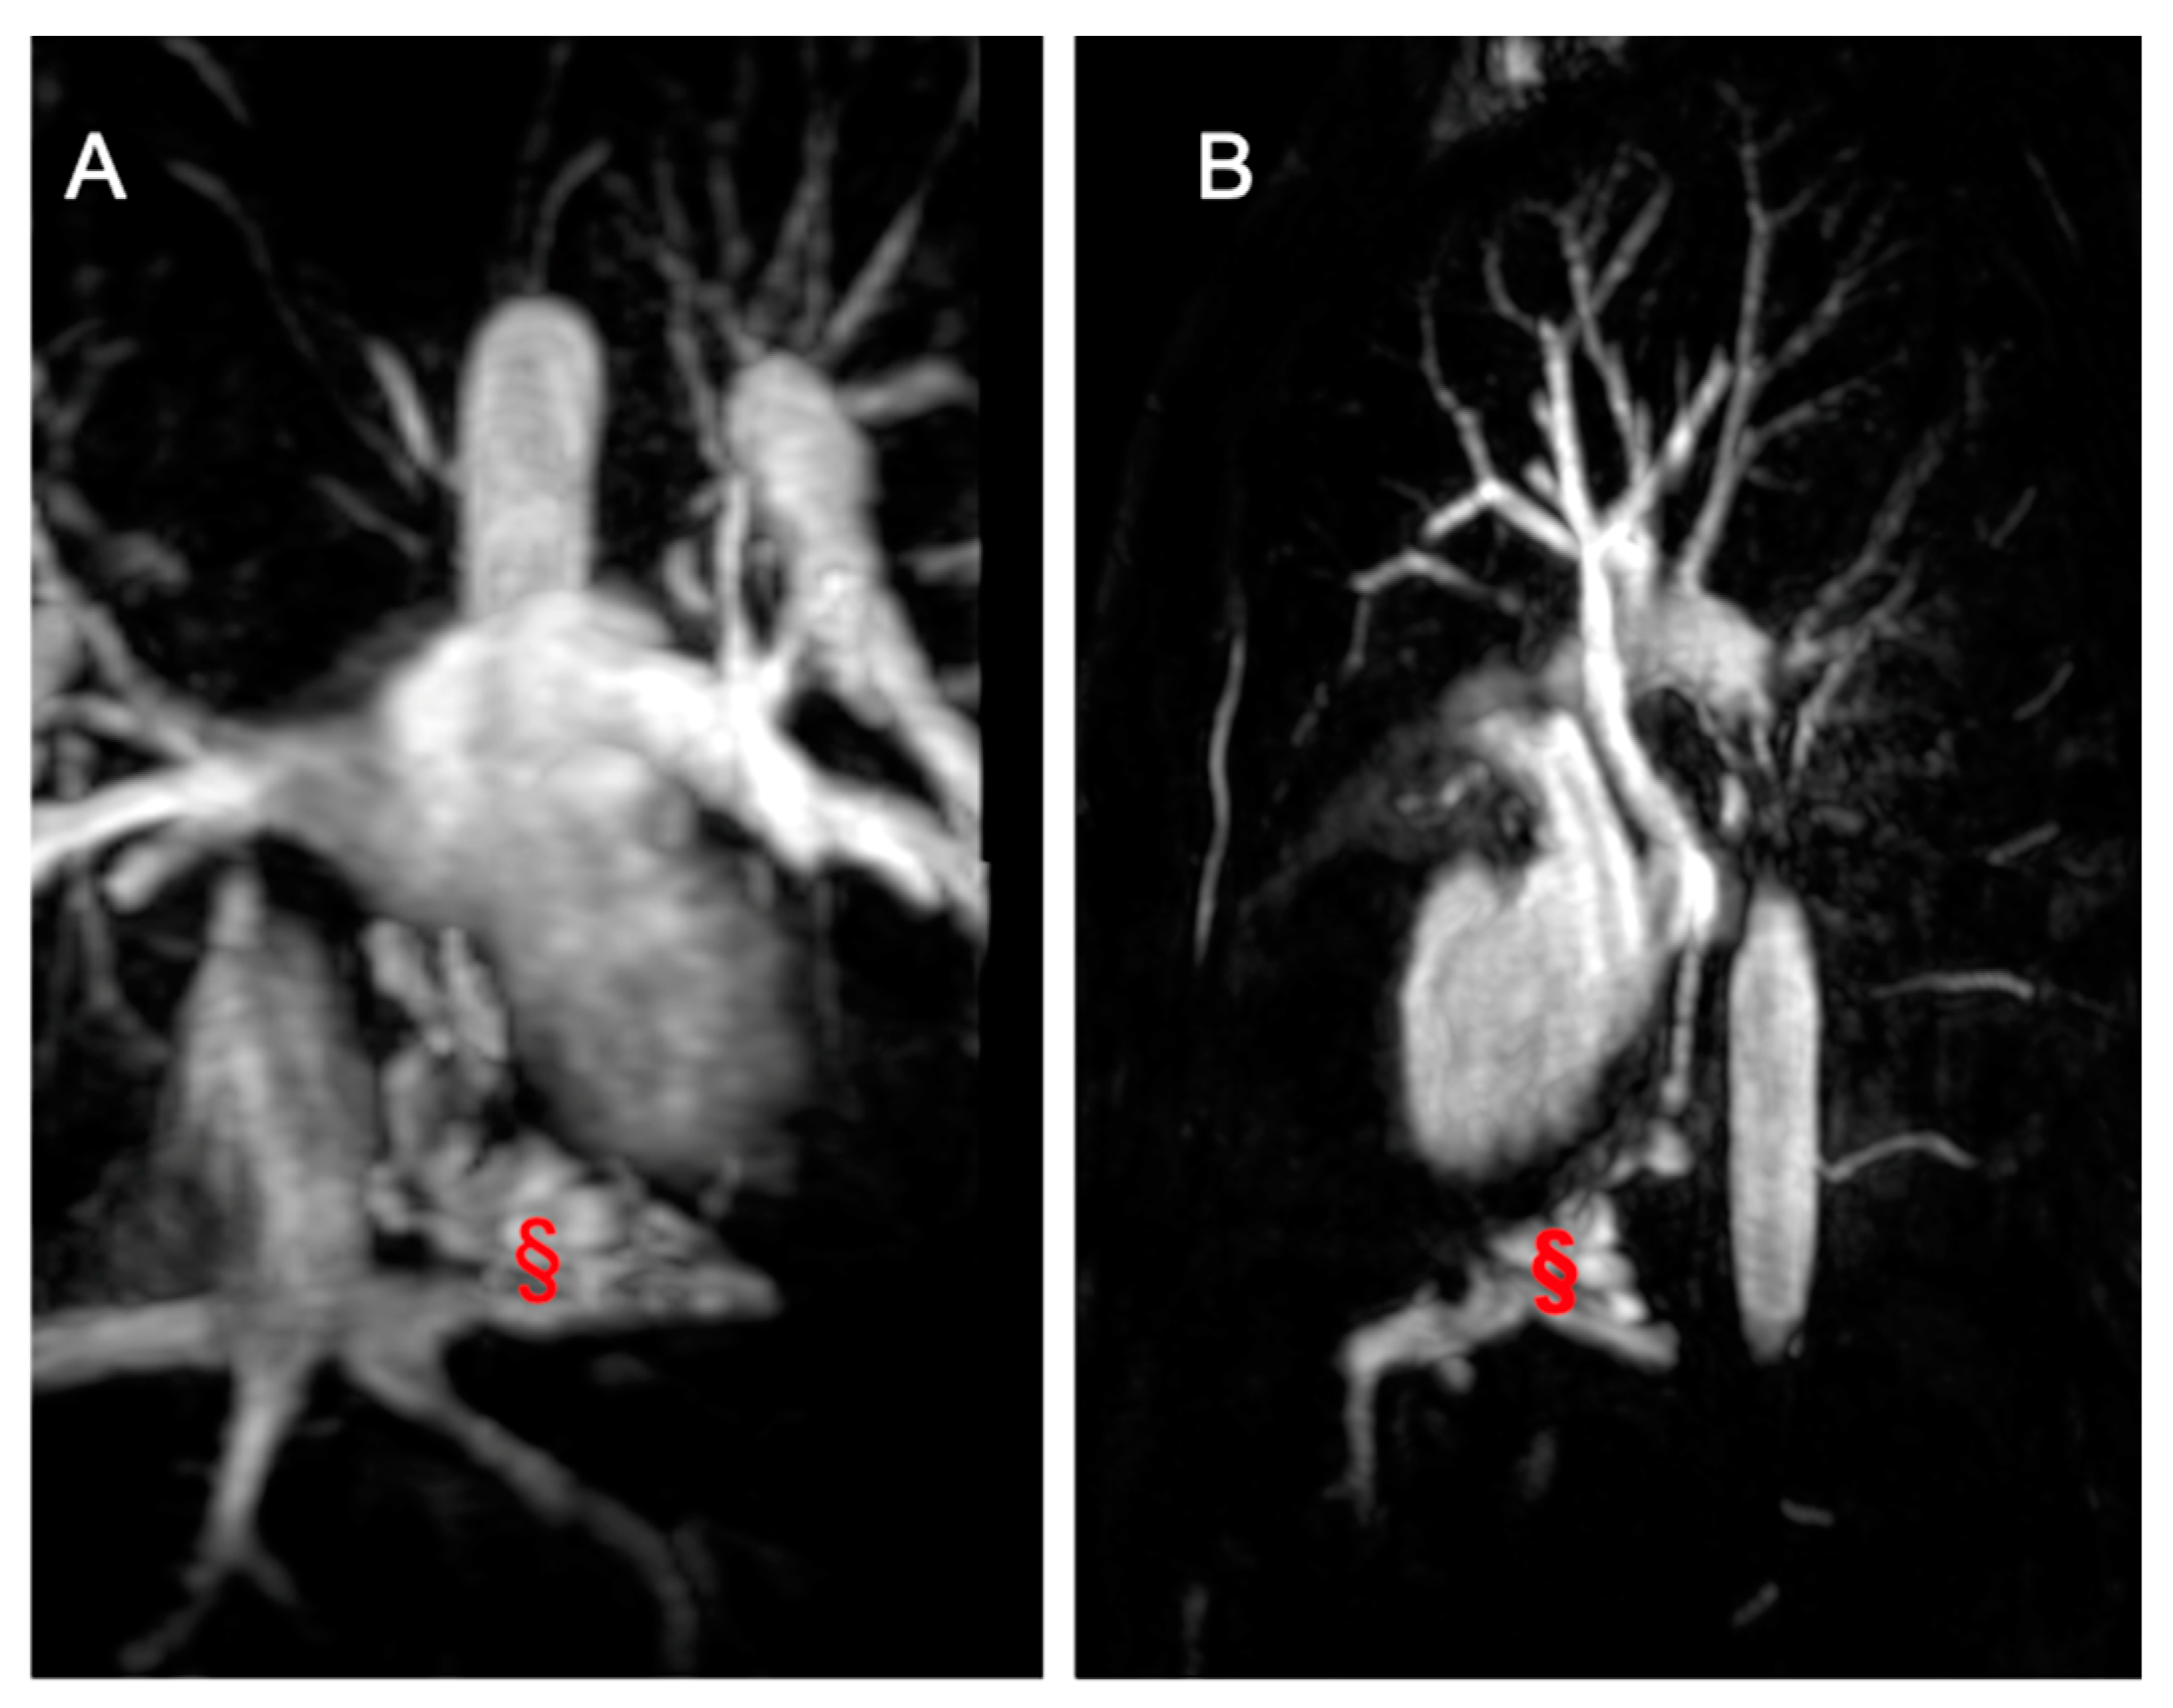

- Leo, I.; Sabatino, J.; Avesani, M.; Moscatelli, S.; Bianco, F.; Borrelli, N.; De Sarro, R.; Leonardi, B.; Calcaterra, G.; Surkova, E.; et al. Non-Invasive Imaging Assessment in Patients with Aortic Coarctation: A Contemporary Review. J. Clin. Med. 2024, 13, 28. [Google Scholar] [CrossRef]